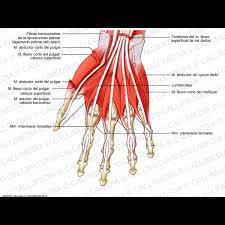

1181 × 1300 - gimolimpo.com

{"id":"Rohz-pKMmS4_0M:","isu":"gimolimpo.com","itg":0,"ity":"jpg","oh":1300,"ou":"http://www.gimolimpo.com/PAGINA%2062/musculosdorsales.jpg","ow":1181,"pt":"ANATOMIA

HUMANA","rid":"KhRkfq-OMAvQ7M","rmt":0,"rt":0,"ru":"http://www.gimolimpo.com/Paginas/ANATOMIA%20HUMANA.htm","s":"Visión

Frontal","sc":1,"th":236,"tu":"https://encrypted-tbn0.gstatic.com/images?q\u003dtbn:ANd9GcQbfHPY9kAjUYom1KfJZWZndoE6JCieaUeZv2ENDRKwDT_ucpXeRQ","tw":214}